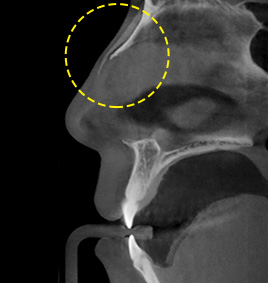

กรณีที่ 2จมูกงุ้มและคดตรงกลาง

ตัดกระดูกและกระดูกอ่อนอย่างเหมาะสมขึ้นอยู่กับระดับความคด